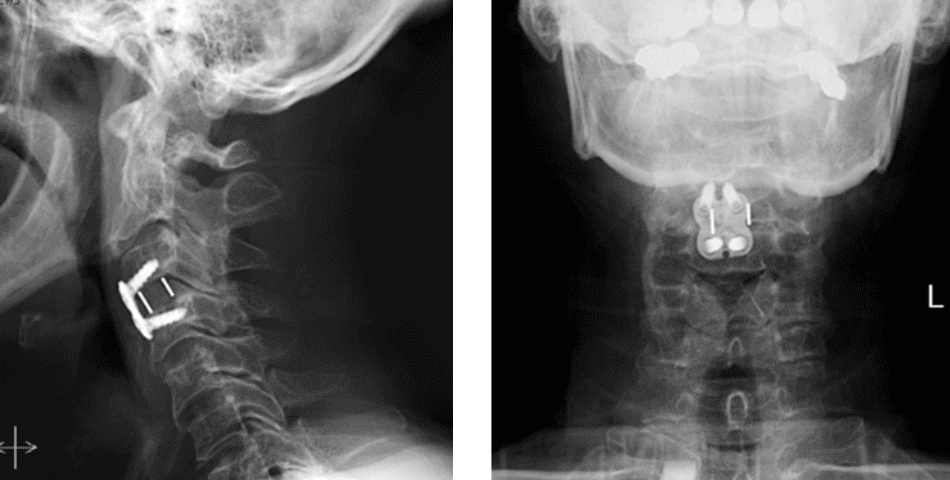

Figure 2. Lateral and AP cervical spine x-rays s/p ACDF